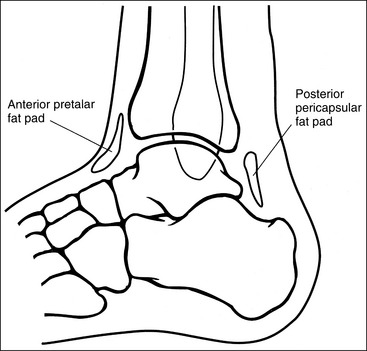

Contrast and density are adequate to demonstrate the anterior pretalar and posterior pericapsular fat pads on the foot and ankle.

• Fat pads on the foot and ankle. Two soft tissue structures located around the foot and ankle may indicate joint effusion and injury, the anterior pretalar fat pad and posterior pericapsular fat pad. The anterior pretalar fat pad is visible anterior to the ankle joint and rests next to the neck of the talus (Figure 6-25). Surrounding the ankle joint is a fibrous, synovium-lined capsule attached to the borders of the tibia, fibula, and talus. On injury or disease invasion the synovial membrane secretes synovial fluid, resulting in distention of the fibrous capsule. Anterior fibrous capsule distention results in displacement of the anterior pretalar fat pad. Because neither the fibrous capsule nor the ankle ligaments can be detected on plain radiography, displacement of this fat pad indicates joint effusion and the possibility of underlying injuries.

• The posterior fat pad is positioned within the indentation formed by the articulation of the posterior tibia and talar bones (see Figure 6-25). This fat pad is displaced in the same manner as the anterior pretalar fat pad, although it is less sensitive and requires more fluid evasion to be displaced.

• Fat pads on the ankle. Two soft tissue structures located around the ankle may indicate joint effusion and injury—the anterior pretalar fat pad and the posterior pericapsular fat pad. The anterior pretalar fat pad is demonstrated anterior to the ankle joint and rests next to the neck of the talus (Figure 6-56). The posterior fat pad, positioned within the indentation formed by the articulation of the posterior tibia and talar bones (see Figure 6-56), is displaced in the same manner as the anterior pretalar fat pad, although it is less sensitive and requires more fluid evasion to be displaced.